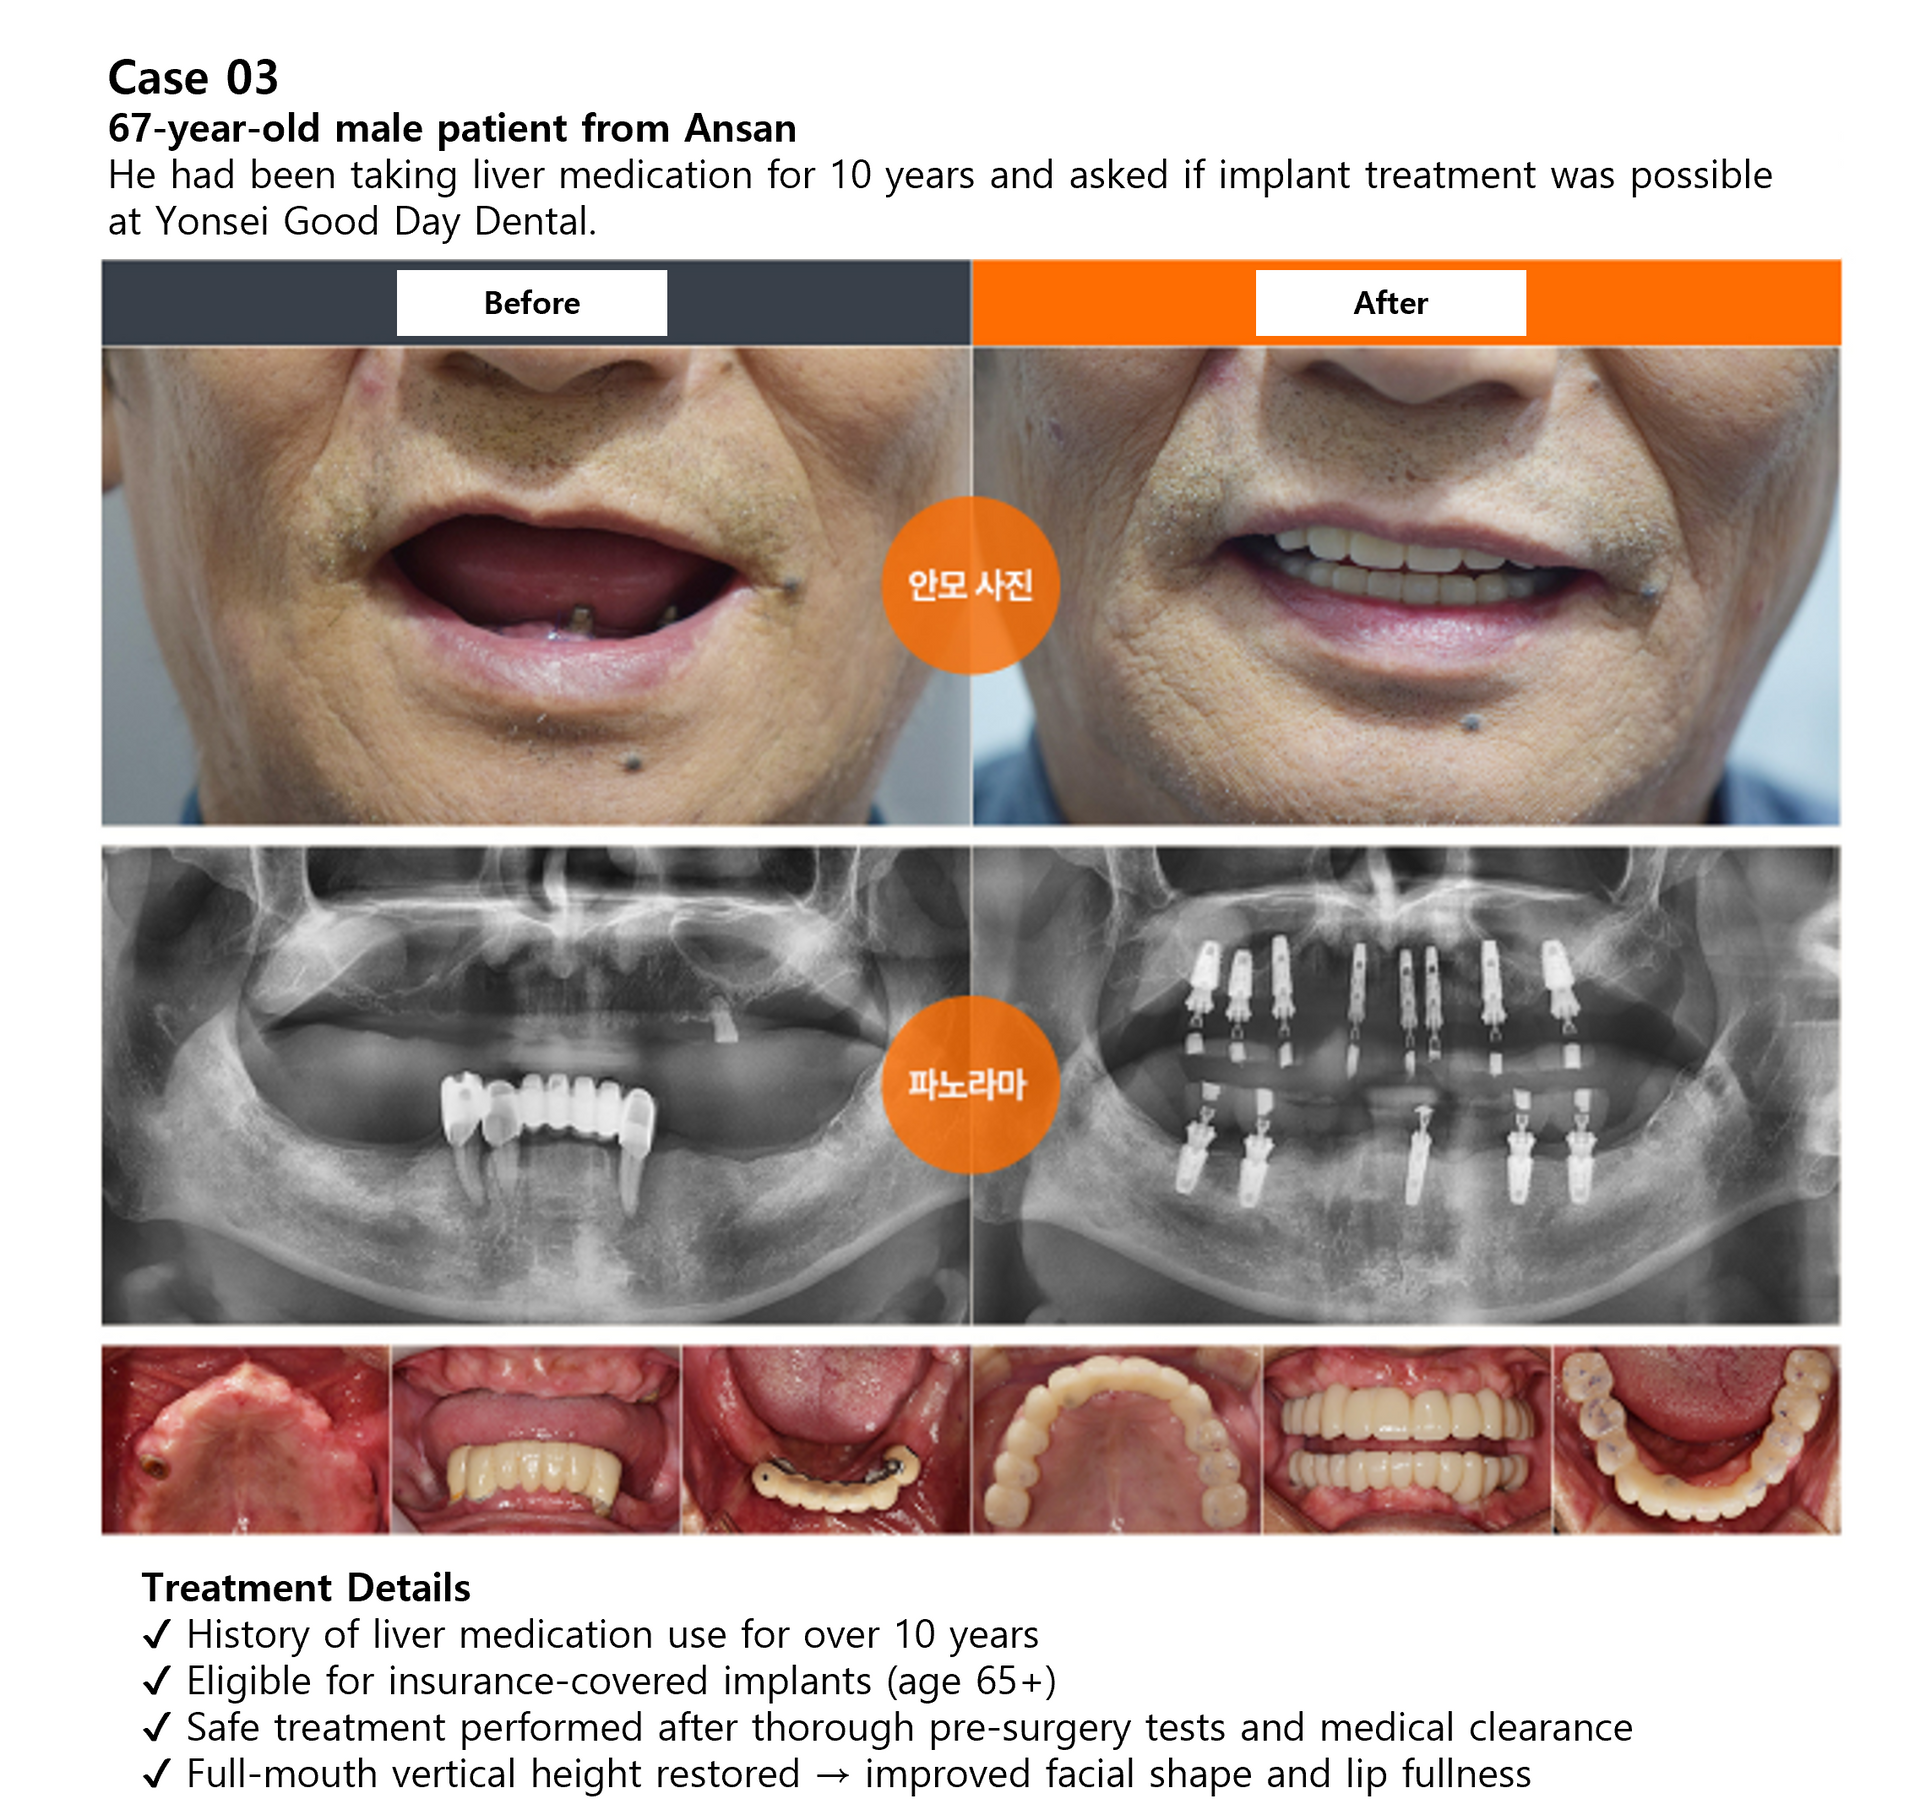

Case Review

Full Mouth Implant Before & After